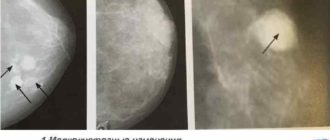

Атерома молочной железы: лечение (удаление) Женская грудь обильно покрыта сальными железами, которые служат плодородной

Диффузная кистозная мастопатия: чем опасна, лечение и симптомы Диффузная кистозная мастопатия, или болезнь Реклю